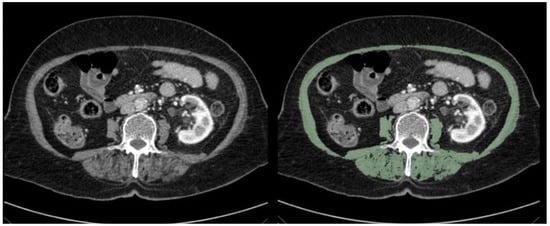

2.2. Assessment of Sarcopenia

| CT | Computed Tomography |